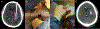

Intracerebral hemorrhage (ICH) is a devastating form of stroke with high morbidity and mortality. This review article focuses on the epidemiology, cause, mechanisms of injury, current treatment strategies, and future research directions of ICH. Incidence of hemorrhagic stroke has increased worldwide over the past 40 years, with shifts in the cause over time as hypertension management has improved and anticoagulant use has increased. Preclinical and clinical trials have elucidated the underlying ICH cause and mechanisms of injury from ICH including the complex interaction between edema, inflammation, iron-induced injury, and oxidative stress. Several trials have investigated optimal medical and surgical management of ICH without clear improvement in survival and functional outcomes. Ongoing research into novel approaches for ICH management provide hope for reducing the devastating effect of this disease in the future. Areas of promise in ICH therapy include prognostic biomarkers and primary prevention based on disease pathobiology, ultra-early hemostatic therapy, minimally invasive surgery, and perihematomal protection against inflammatory brain injury.